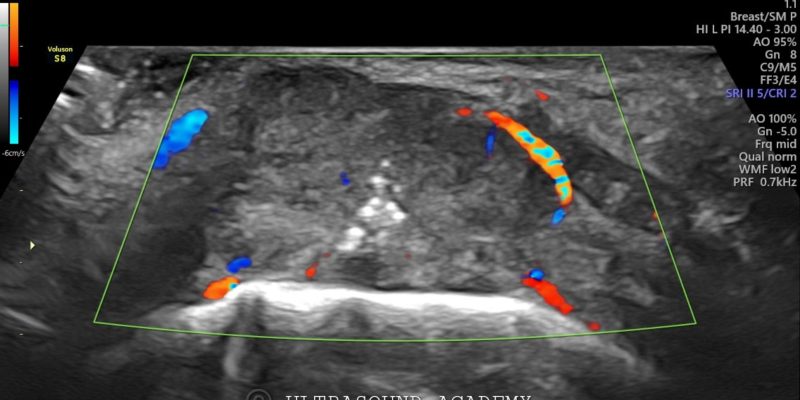

• Hypoechoic irregular mass measuring approximately Approx 1.5 cm in greatest dimension located in the left buccal mucosa.

• The mass shows heterogeneous echotexture with poorly defined borders, invading into the adjacent soft tissues.

• Increased vascularity seen within the lesion on color Doppler.

• Also an ulcer with air foci seen as hyperechoic specks.